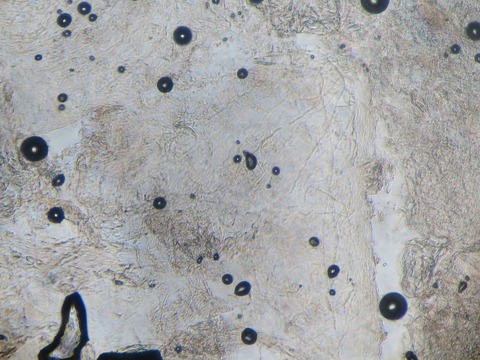

顕微鏡写真です。

細い糸の様な線が白癬菌です。

糸状菌と言われます。